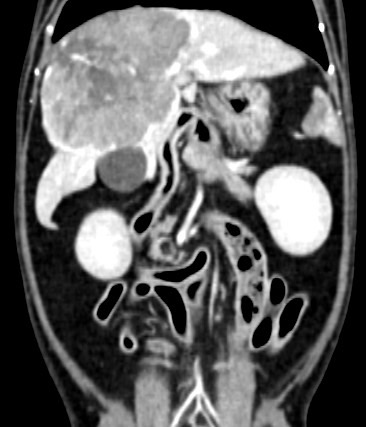

卵巢殘留

卵巢殘留是指雌性動物在進行絕育手術後,仍然有部分卵巢組織殘留,進而導致術後仍然反覆發情,並可能繼發子宮殘端蓄膿、乳腺腫瘤等疾病。而殘存的卵巢,由於體積小且子宮角已被摘除,往往難以找尋。幸而隨著動物醫療進步,依靠電腦斷層、內視鏡等先進設備,卵巢殘留的情況已不再難以處理。

小花是一隻一歲多的母貓,半年前曾在其他醫院做過絕育手術,但手術當下卻只找到單側的子宮卵巢,且在這半年當中仍然反反覆覆地發情,讓飼主十分擔心,於是來到築心尋求治療。在了解小花的狀況後,我們為小花安排了電腦斷層掃描,並在腹腔的左側發現了疑似殘存的卵巢影像(見圖示),接著,在影像定位的協助下順利開腹取出殘存的卵巢和發育異常子宮角,而在殘存的子宮內已然形成了子宮蓄膿。

幸虧子宮蓄膿的情形尚不嚴重,並沒有造成感染範圍的擴散,手術後經過一小段時間的修養,小花目前已經順利拆線,在家過著無憂無慮的生活囉。